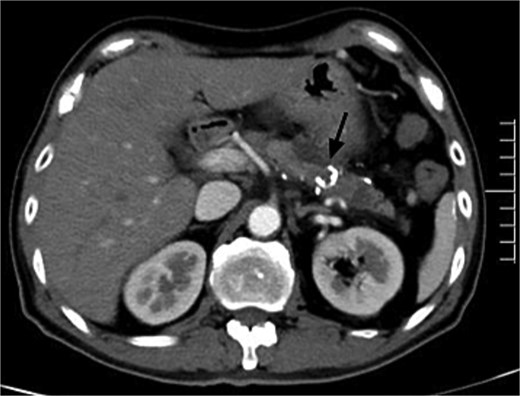

For further diagnosis and treatment, angiography and embolization under local anesthesia were agreed on. Celiac and superior mesenteric angiography through the right femoral approach confirmed PVAM which mainly originated from great pancreatic artery (Fig. 2a) and superior mesenteric artery (Fig. 2b). Selective embolization of great pancreatic artery was performed using a mixture of n-butyl-2-cyanoacrylate (NBCA) (Histoacryl; Compont, Beijing, China) and iodized oil (Poppy Ethidium, Hengrui, Jiangsu, China) combined in a 1:3 ratio. After the embolization, repeat angiography showed significant regression of the PVAM (Fig. 2c). Because selectively catheterizing the major feeding branch of superior mesenteric artery failed through the right femoral approach, embolization using the same mixture was done through the right radial approach. After the embolization, only minimal residual staining of the pancreas can be seen (Fig. 2d). The clinical outcome was good, the patient suffered mild abdominal pain for 2 days and no severe embolization-related complications, and was discharged 4 days after the procedure. Follow-up CT scan after 8 months demonstrated progressive regression of the PAVM (Fig. 3). At the time of writing this manuscript, the patient had completed 32 months of follow-up and had no recurrent AP or abdominal pain.

Postembolic enhanced CT after 7 months showed disappearance of PAVM with high-density spots (NBCA) in the pancreas (black arrow).